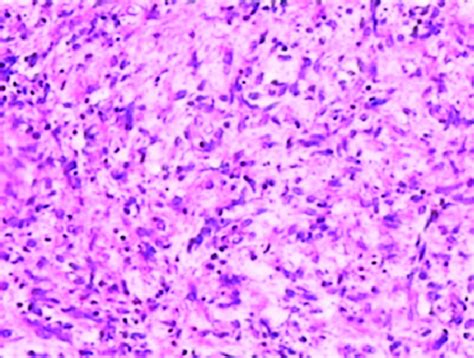

Let’s zoom in even further and talk about what a pathologist actually sees under the microscope when they identify pseudopalisading pleomorphic tumor cells . This is where the magic of histopathology truly shines. When a biopsy or surgical specimen arrives in the lab, it’s meticulously processed, sliced incredibly thin, stained with various dyes, and then examined under high magnification. The pathologist’s trained eye is looking for specific architectural and cytologic features. In the case of pseudopalisading, they’ll observe areas where the tumor cells aren’t just scattered randomly. Instead, they’ll see distinct regions where the nuclei (the control centers of the cells) are densely packed and aligned in a linear fashion, often surrounding a central area that looks pale or empty. This pale or empty area is the necrotic tissue – the dead or dying cells. The tumor cells themselves will often appear quite abnormal. Pleomorphism is the operative word here. You’ll see a wide range of nuclear shapes – some might be round, others oval, and some could be very irregular or elongated. The size of the nuclei will also vary significantly. Furthermore, the cells might have prominent nucleoli (small structures within the nucleus) and abundant cytoplasm (the material surrounding the nucleus). The chromatin (the genetic material within the nucleus) might be coarse and clumped, indicating active and abnormal cellular activity. This pattern – the dense, aligned tumor cells bordering necrotic zones, coupled with the significant variation in cell and nuclear morphology – is what strongly suggests pseudopalisading. It’s a very specific visual cue. Other less aggressive tumors might show cellularity, but they usually lack this striking alignment around necrosis and the degree of pleomorphism. This detailed microscopic examination is absolutely crucial for differentiating between tumor types and grades, directly impacting how a patient is treated. It’s like being a detective, piecing together clues from the cellular level.